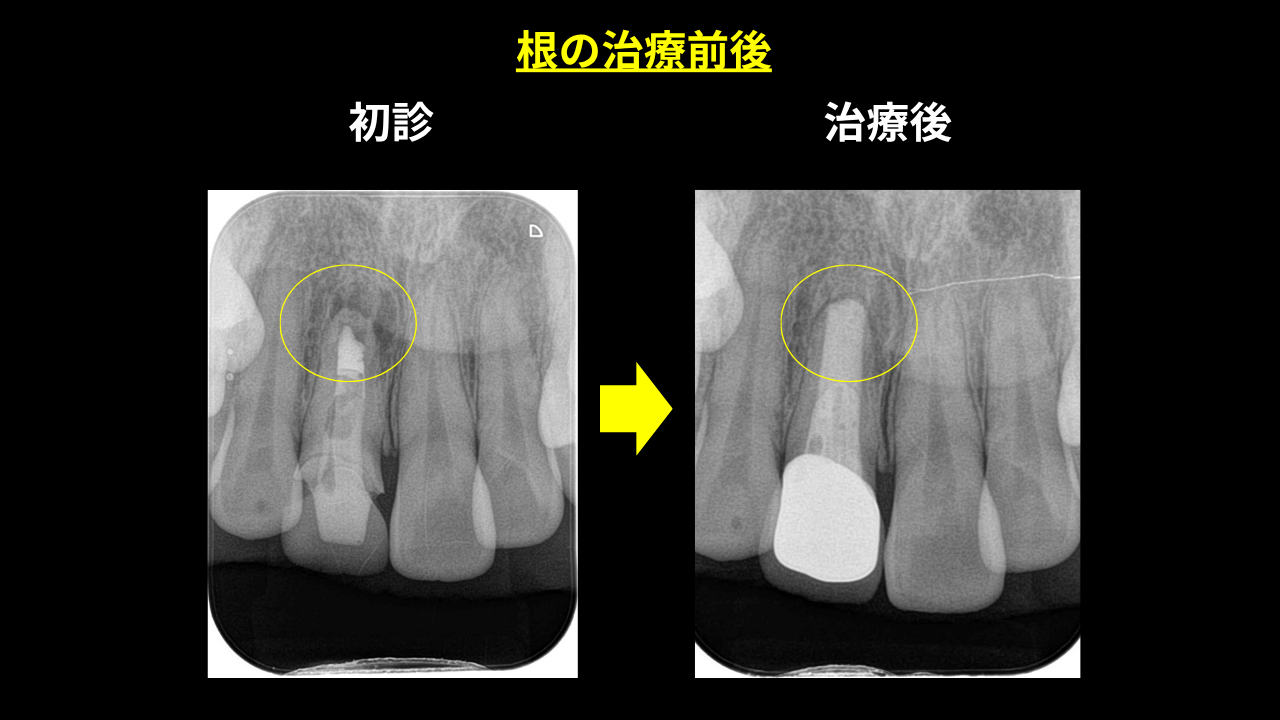

お口の中を確認すると、差し歯の根元に黒ずみがあり、歯茎との境目が目立つ状態でした。レントゲンを撮影すると、根の先端に細菌感染による病巣(黒い影)が確認されました。

根管治療後のレントゲンでは、根の先端にあった黒い影(病変)が消え、骨が再生されていることが確認できました。

差し歯の交換は、しっかり根管治療を行うことで、根の先のバイ菌もなくなり、骨が戻ってきます。これなら今後もしっかり咬める状態が続きます。